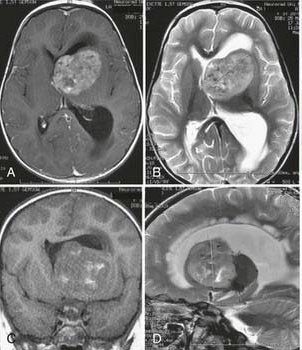

56岁男性,因持续加重的弥漫性头痛、眩晕、排尿障碍及顽固性呃逆就诊。影像学检查显示中脑顶盖区及第三脑室后部存在明显占位性病变。尽管该部位手术风险极高,毗邻重要神经核团和脑脊液循环通路,但考虑到患者症状进行性加重,神经外科团队最终决定实施肿瘤全切除术。术中运用先进的神经导航和实时电生理监测技术,成功在保护关键神经结构的前提下完成肿瘤全切。术后病理确诊为孤立性纤维瘤,随访显示患者症状完全缓解且未出现任何新增神经功能缺损。

术前MRI

术后MRI